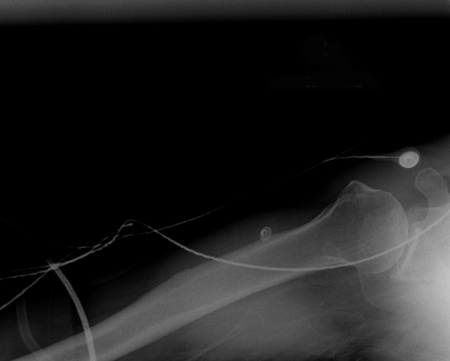

Incidência anteroposterior de radiografia de luxação do cotovelo reduzida

Acervo pessoal do Dr. Paul Novakovich